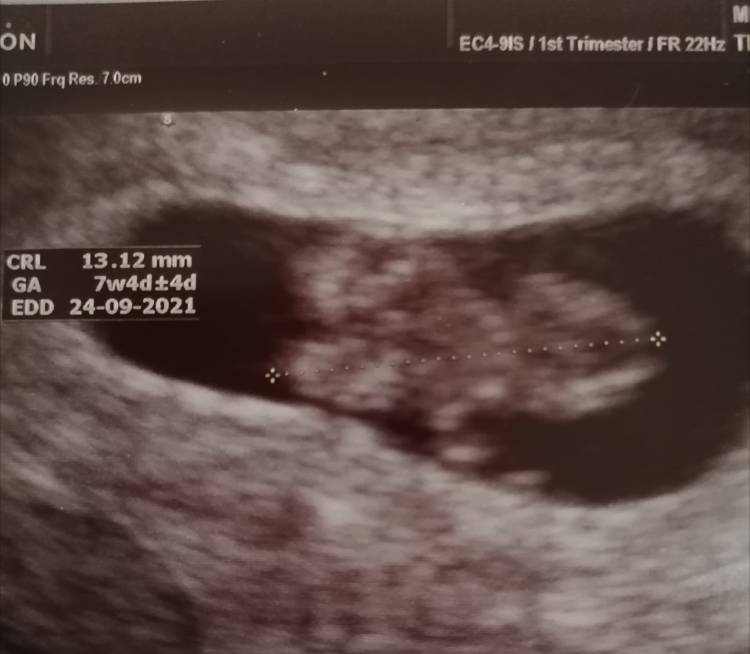

A jednak cuda się zdarzają[emoji16][emoji3590] Jestem po wizycie i serduszko bije[emoji177] kupa badań do zrobienia i oszczędzający tryb ale będzie warto[emoji847] Nasze maleńkie szczęście w nieszczęściu [emoji16][emoji1768]

IMG_20210209_222852.jpeg